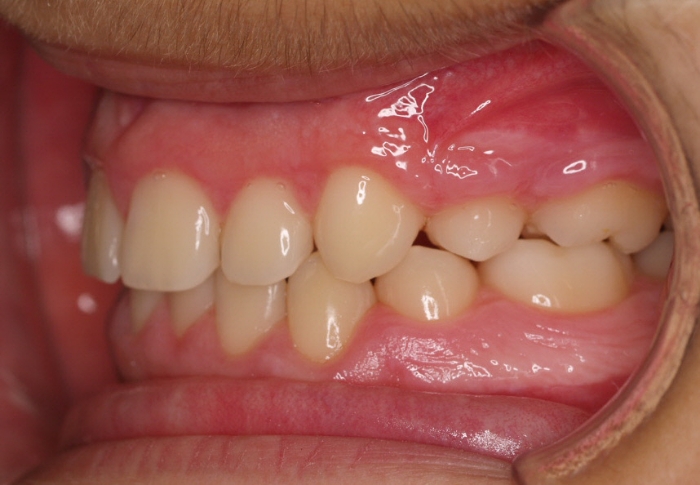

El paciente M.C. acude a nuestra consulta por:

– Apiñamiento importante

– Perfil convexo

– Forma arcada estrecha

-sobremordida

Con lo que decide realizarse un tratamiento de ortodoncia de duración de 26 meses con brackets smartclip 022 de acero.

Fotos antes tratamiento: